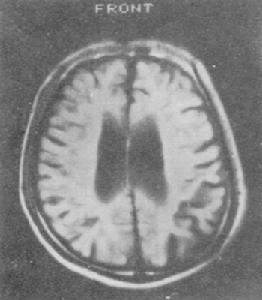

④血及腦脊液常規檢查無異常,CT、MRI檢查也無特徵性所見。